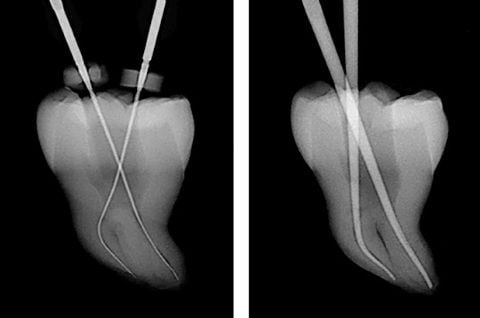

根管長測定器

根管長測定器とは、抜髄、感染根管処置の治療の際に用いる測定装置です。

抜髄、感染根管処置の治療は、根尖部までしっかりと感染物質を除去する必要があり、そのためには湾曲している根の正確な長さの把握が不可欠となります。

根管長測定器は口腔粘膜と根管内に挿入した測定電極の先端との間のインピーダンス値を測定することにより、根の長さを把握する装置です。